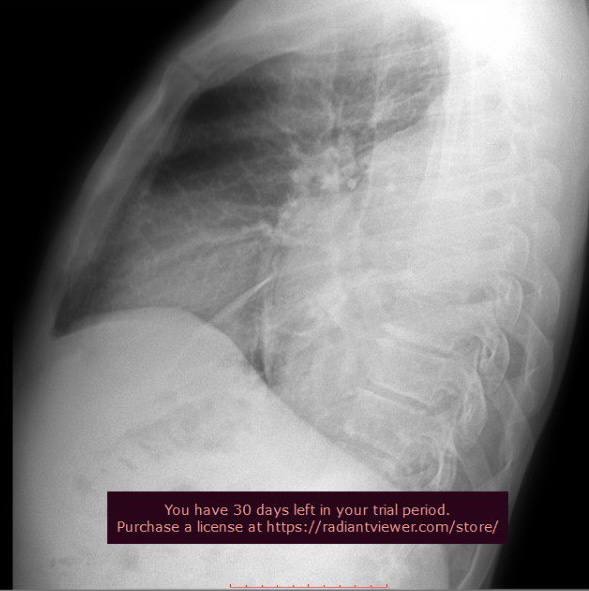

На рентгенограмі ОГК в прямій та боковій проекціях візуалізується рівномірне зниження повітряності у середньому та нижньому полі зліва, на бічній інтенсивне затемнення основою донизу в задніх та середньонижньому відділі ( від 4 ребра до заднього синуса). Легеневий малюнок незначно посилений. Корені легень структурні. Діафрагма без змін. Тінь серця та аорти в межах норми.